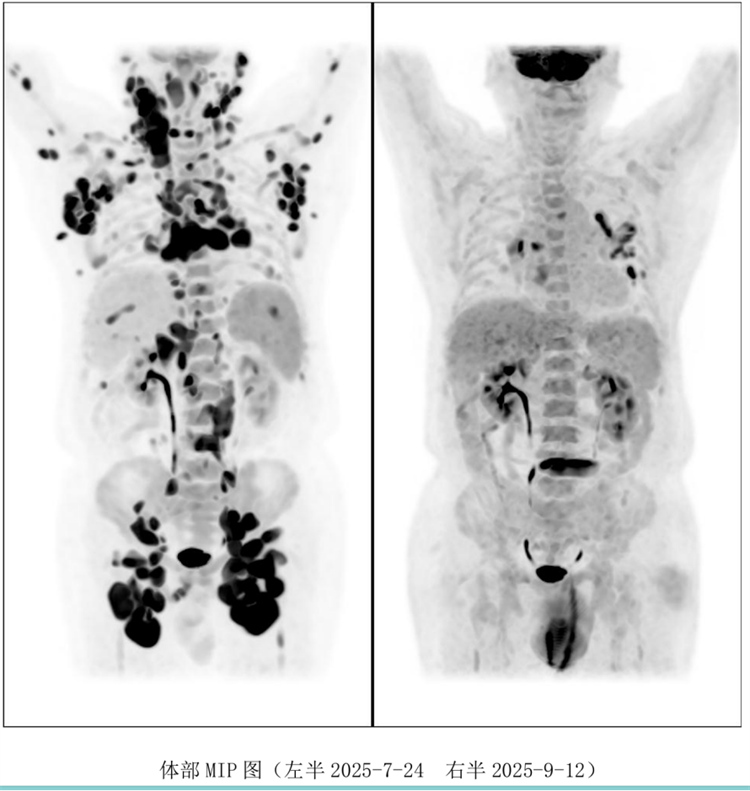

病例匯報(bào)環(huán)節(jié)由我院淋巴瘤科張薇醫(yī)生帶來(lái)了三例精彩紛呈的難治復(fù)發(fā)彌漫大B淋巴瘤CAR-T治療的病例。

病例過(guò)程跌宕起伏,從橋接治療到靶點(diǎn)的選擇,并發(fā)癥的處理都極具代表性。張醫(yī)生詳盡分享了患者在治療過(guò)程中的挑戰(zhàn)、決策依據(jù)以及CAR-T細(xì)胞治療后的驚人緩解與轉(zhuǎn)歸,充分展示了CAR-T技術(shù)為晚期患者帶來(lái)的突破性生存希望。